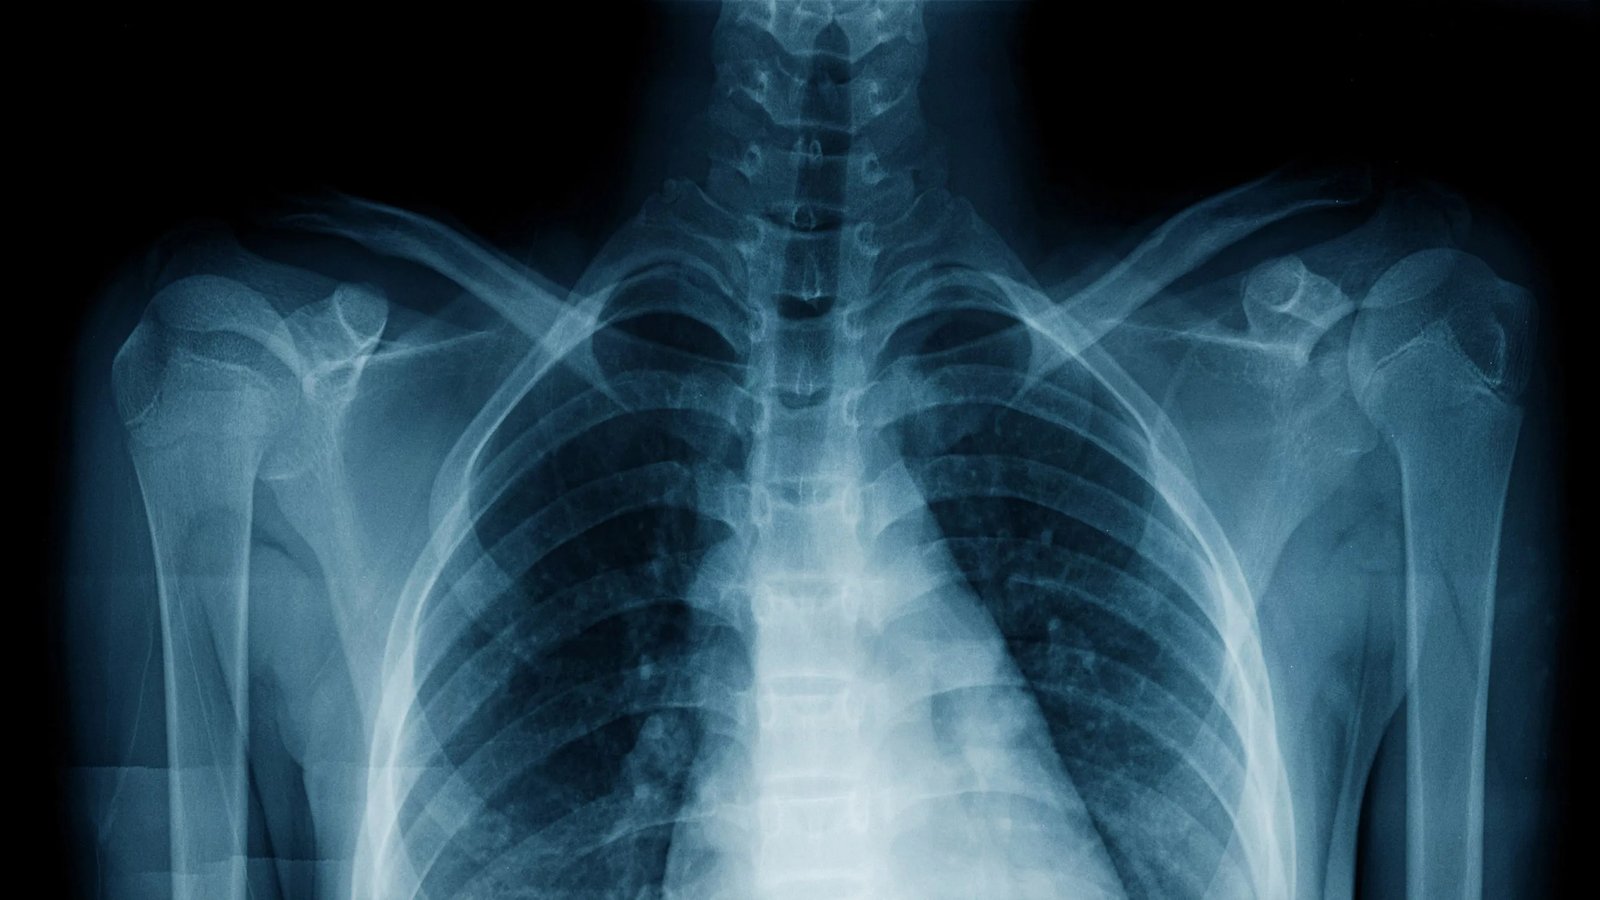

2017 yılına ait CheXNet modelinin tanıtımı, 100.000’den fazla akciğer röntgeni üzerinde gerçekleştirildi ve zatürreyi sertifikalı uzmanlardan oluşan bir kurula göre daha yüksek doğruluk oranıyla tespit edebildi. Üstelik bu sistem hızlı, ücretsiz ve yalnızca tek bir tüketici sınıfı GPU üzerinde çalışabiliyor. Hastaneler bu teknoloji sayesinde yeni bir taramayı bir saniyeden kısa sürede sınıflandırabiliyor.

O zamandan sonra Annalise.ai, Lunit, Aidoc ve Qure.ai gibi şirketler, çeşitli taramalarda yüzlerce hastalığı teşhis eden modeller geliştirdi. Bazı ürünler, kritik vakaların önceliklendirilmesi için radyologların iş listelerini yeniden düzenleyebilir, bakım ekiplerine sonraki adımları önerir veya hastane kayıt sistemine entegre raporlar hazırlayabilir. Hatta LumineticsCore, doktor onayı olmadan da kullanılabiliyor. Günümüzde FDA onaylı 700’den fazla radyoloji modeli mevcut ve bu rakam tüm tıbbi yapay zeka sistemlerinin dörtte üçünü kapsıyor.